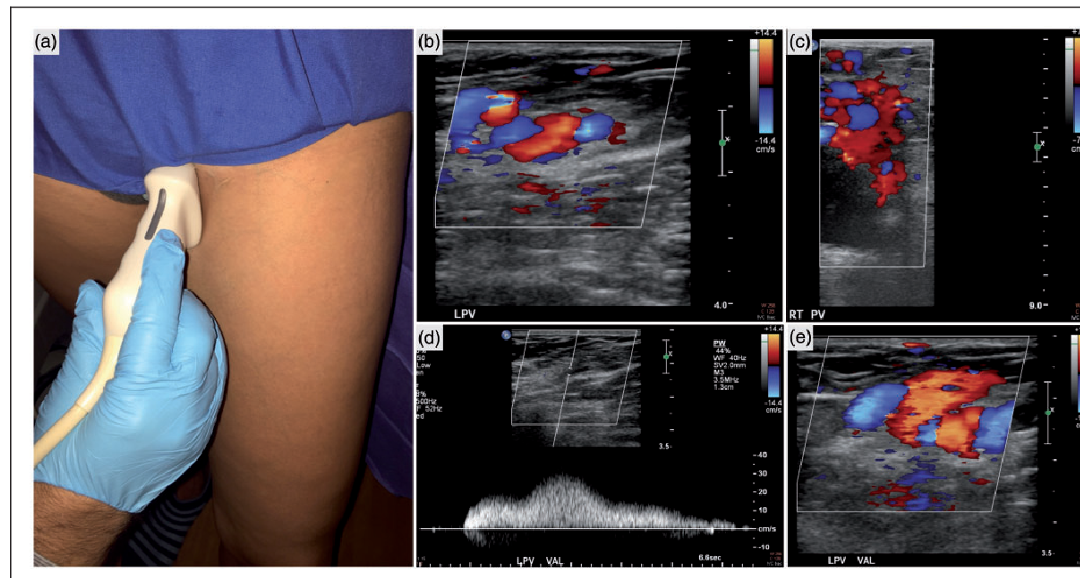

- Xác định nhiều cấu trúc tĩnh mạch giãn xung quanh tử cung (tránh nhầm lẫn với ứ dịch vòi trứng) – chẩn đoán giãn khi đường kính tĩnh mạch quanh tử cung trên 4mm, đường kính tĩnh mạch buồng trứng giãn trên 6mm.

- Vận tốc dòng chảy trong các nhánh tĩnh mạch thấp dưới 3cm/s hoặc có dòng trào ngược sau khi sử dụng nghiệm pháp Valsava (trên 1s).

- Hỗ trợ chẩn đoán tốt hơn khi tìm thấy các nguyên nhân chèn ép, thấy vòng nối bàng hệ hai bên vắt qua phía trước hoặc sau tử cung trên CT, MRI.